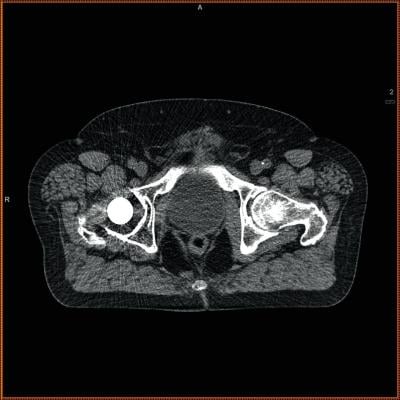

The researchers evaluated the CTs with additional measurements of the size and density of lumbar and thoracic muscle alongside the spine. That information was then compared with mortality data from the National Death Index, a centralized database of death record information maintained by the U.S. Centers for Disease Control and Prevention.

The results showed that patients with better core muscle had significantly better survival rates over the duration of the 10-year study.